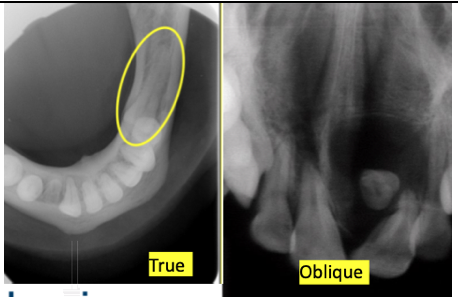

Name this type of radiograph?

Occlusal. There are 2 types:

What are the soft tissue checkpoints for a maxillary occlusal radiograph?

Alatragus line should be paralell to the floor

what are the soft tissue checkpoints for a mandibular occlusal?

Corner of the mouth to the tragus of the ear are parallel.

Head is tilted backwards.